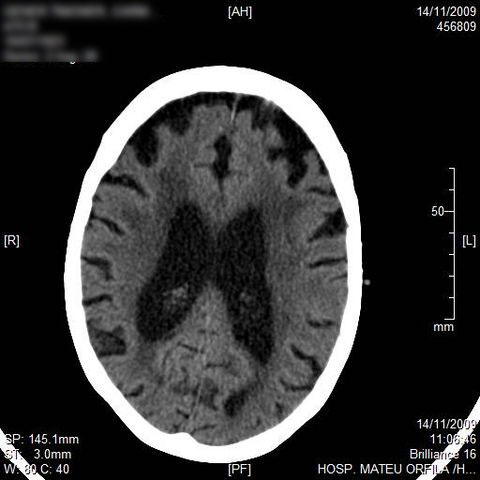

AVC amplio de territorio de A. cerebral media

Atrofia cortico-subcortical de predominio frontotemporal.